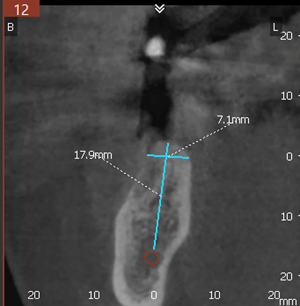

Paciente do sexo feminino, 61 anos, chegou ao consultório com ausência do dente 36, porém com boa quantidade e qualidade (7.1 mm de diâmetro e 17.9 mm de altura) de remanescente ósseo. A mesma reside no Canadá e retornaria ao país de origem após 30 dias. Devido ao pouco tempo disponível, optou-se pela utilização do Implante Maestro Cone Morse, que permite uma reabilitação protética final precoce.

Levando em conta a região e o tipo de reabilitação, o implante selecionado foi o Due Cone Maestro de medida 4 X 11mm.